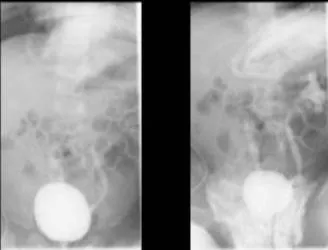

VCUG尿路逆流攝影看出左右兩側輸尿管都有逆流情況。翻攝畫面

有些新生兒泌尿道系統若有缺陷,而有尿液從膀胱逆流到輸尿管的情形,也可能造成泌尿道感染。而女生天生尿道較短,泌尿道感染機率也較高,因此女嬰反覆感染兩次以上,就應該做輸尿管逆流攝影檢查以確認有無異常。

楊岱璟醫師建議,新生兒泌尿道感染若未及時治療,細菌在反覆發燒下,也可能進入血液,引發敗血症甚至休克!嚴重嬰幼兒泌尿道感染也必須使用抗生素治療至少五到七天,同時安排腎臟超音波檢查是否有腎盂擴大現象,必要時安排輸尿管逆流攝影以了解泌尿道發育狀況。不論是哪一階段療程,都要經過醫師評估,做最適當的處置,以確保嬰幼兒健康順利恢復。